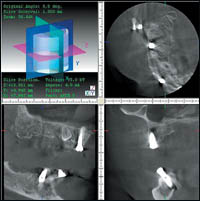

— дает возможность выявлять патологические изменения со стороны верхнечелюстных пазух, полости носа, нижнечелюстного канала (рис. 7);